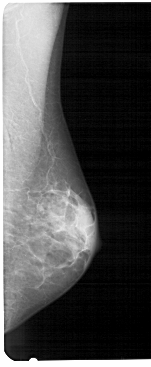

A_1937_1.LEFT_CC

LEFT_CC LINES 4891 PIXELS_PER_LINE 2281 BITS_PER_PIXEL 12 RESOLUTION 43.5 OVERLAY